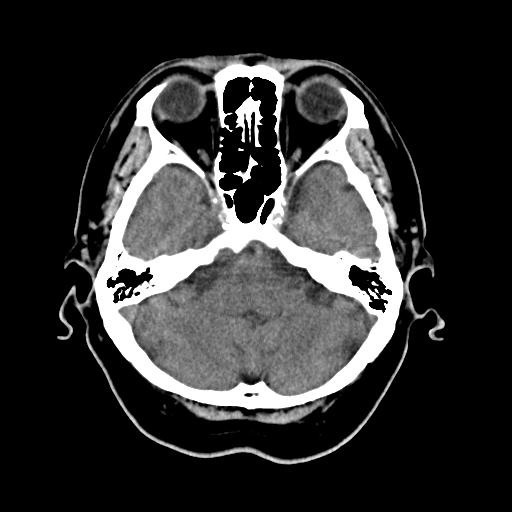

で、頭部のCT画像ファィルを、Gif-Aniを作った。

そのアニメは、 ここです。

朝から、妻に連れられて「人間ドック」へ。

オプションのCTを3種類も頼んだので・・・「ン」万円アップ。

「画像データをくれるかと聞いて、くれたら受ける」といったので、「発注」しました。

一部は紙データ、他はCDで渡すということで、頼みました。

1,2週間で送られてくるそうです。